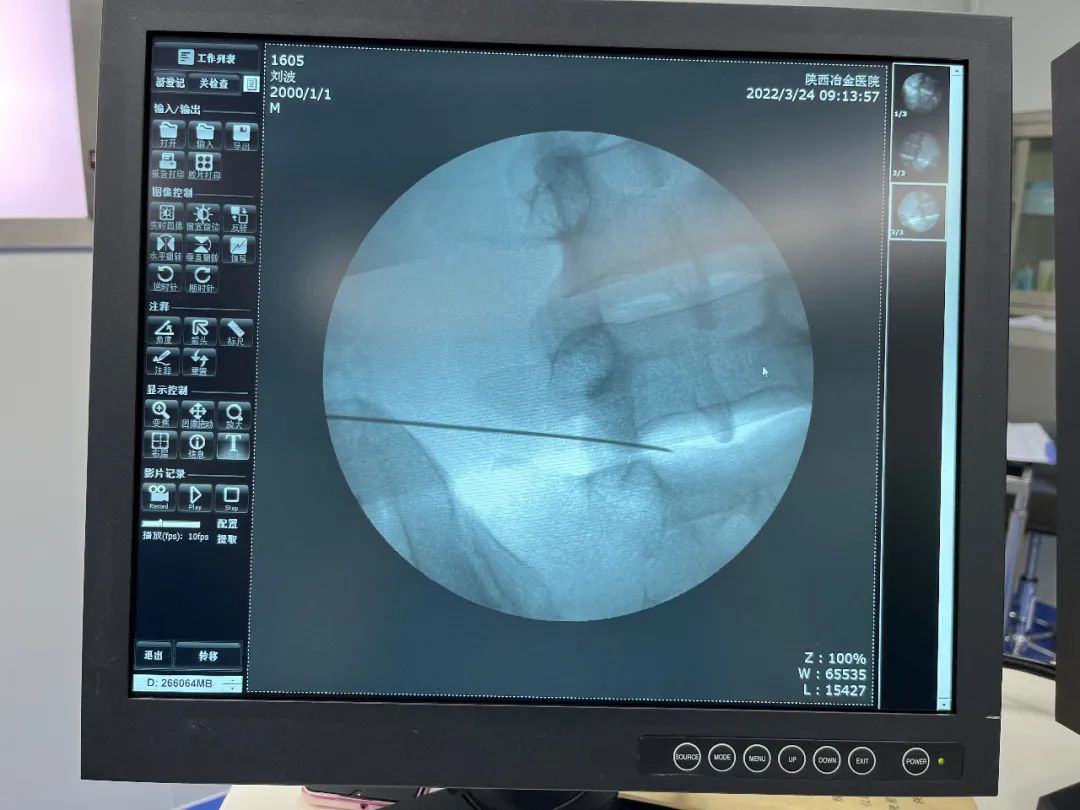

3月24日上午09点,陕西冶金医院骨科赵学刚主任及吕艳主治医师为患者成功实施经皮穿刺腰椎间盘射频消融术,手术顺利,术后症状立刻消失,患者自行走回病区。

经皮穿刺腰椎间盘射频消融手术,局部麻醉,C型臂透视下定位,精准消融,无切口,痛苦小,安全无损害,效果显著,手术20分钟,患者不需要禁食,术后不影响正常生活、工作。